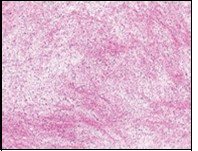

Macroscopically,the neoplasm is gradually progressive, painless, firm, tan coloured, well circumscribed, grossly infiltrative, soft tissue mass of magnitude varying from one centimetre to 18 centimetres, commonly of 6 centimetres diameter. Cut surface is fibrotic with focal myxoid areas4. On fine needle aspiration cytology, the cellular neoplasm is configured by spindle-shaped cells. Tumour cells contain scant, wispy cytoplasm, uniform, elongated nuclei and miniature, inconspicuous nucleoli. The background is prominently myxoid. Significant nuclear pleomorphism or mitotic activity is absent. However, cogent diagnosis on cytology may be challenging 4.5. On low power, the well demarcated neoplasm is composed of alternating foci of myxoid and fibrous tissue. Giant rosettes are intermingled with zones of whorled cellular aggregates recapitulating preliminary rosettes.

Bland tumour cells depict monotonous, hyperchromatic nuclei. Tumour areas can exhibit prominent curvilinear, arching or plexiform vasculature. Mitotic activity is exceptional 4, 5.

Typically, low grade fibromyxoid sarcoma is comprised of a whorled cellular pattern with intermingled fibrous and myxoid areas. Also, minimally cellular areas of collagenous tissue are denominated, composed of uniform spindle-shaped cells4, 5. Unique morphologic pattern of hyalinising spindle cell tumour configuring giant rosettes can appear in certain low grade fibromyxoid sarcomas4, 5.

The minimally to moderately cellular neoplasm is composed of bland, fusiform or spindle-shaped cells with scarce cytoplasm and angulated nuclei. Also, whorled cellular aggregates are exhibited. Focal to diffuse cellular whorls are intermingled within a dense, collagen-rich stroma. Abrupt, focal transition to myxoid areas can be discerned. Roughly 45% neoplasms depict foci of epithelioid cells. Nearly 40% tumours display enlarged, inadequately configured collagen rosettes2, 4.

The neoplasm frequently infiltrates abutting skeletal muscle. Occasionally, tumefaction denominates hyper-cellular foci, tumour necrosis, cellular or nuclear atypia and mitotic figures, features which are characteristic of intermediate to high grade sarcoma. Localized tumour reoccurrence may be hyper-cellular with enhanced mitotic activity 4, 5. On ultrastructural examination, fibroblastic differentiation is exemplified 5. Figure 1, Figure 2, Figure 3, Figure 4, Figure 5, Figure 6, Figure 7, Figure 8.

Figure 2.Low grade fibromyxoid sarcoma exemplifying intermingled foci of fibrous and myxoid regions of spindle-shaped cells with minimal pleomorphism and absence of mitosis (10).

Figure 3.Low grade fibromyxoid sarcoma demonstrating alternating fibrous and myxoid areas comprised of uniform spindle-shaped cells (11).

Figure 4.Low grade fibromyxoid sarcoma composed of alternating foci of fibrous and myxoid region with interwoven fascicles and bland spindle-shaped tumour cells (12).

Figure 5.Low grade fibromyxoid sarcoma exhibiting alternating fibrous and myxoid zones composed of spindle-shaped tumour cells (13).